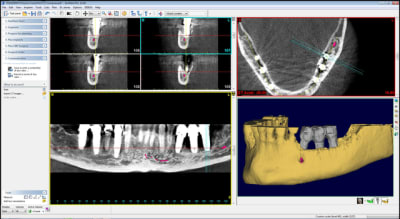

quelques images en 3 D...